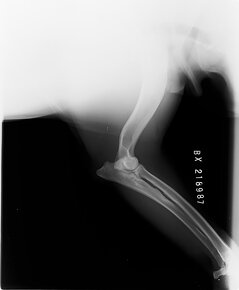

Hledáme nevěstu pro mladého psa BD s PP, Butch Coolidge dei Mastini del Goya, import Itálie, DKK AA, DLK 00, srdce OK, vyšetření sperma, vynikající pohyb, V1, CAC, Národní vítěz ČR, stáří 3 roky, perfektní povaha